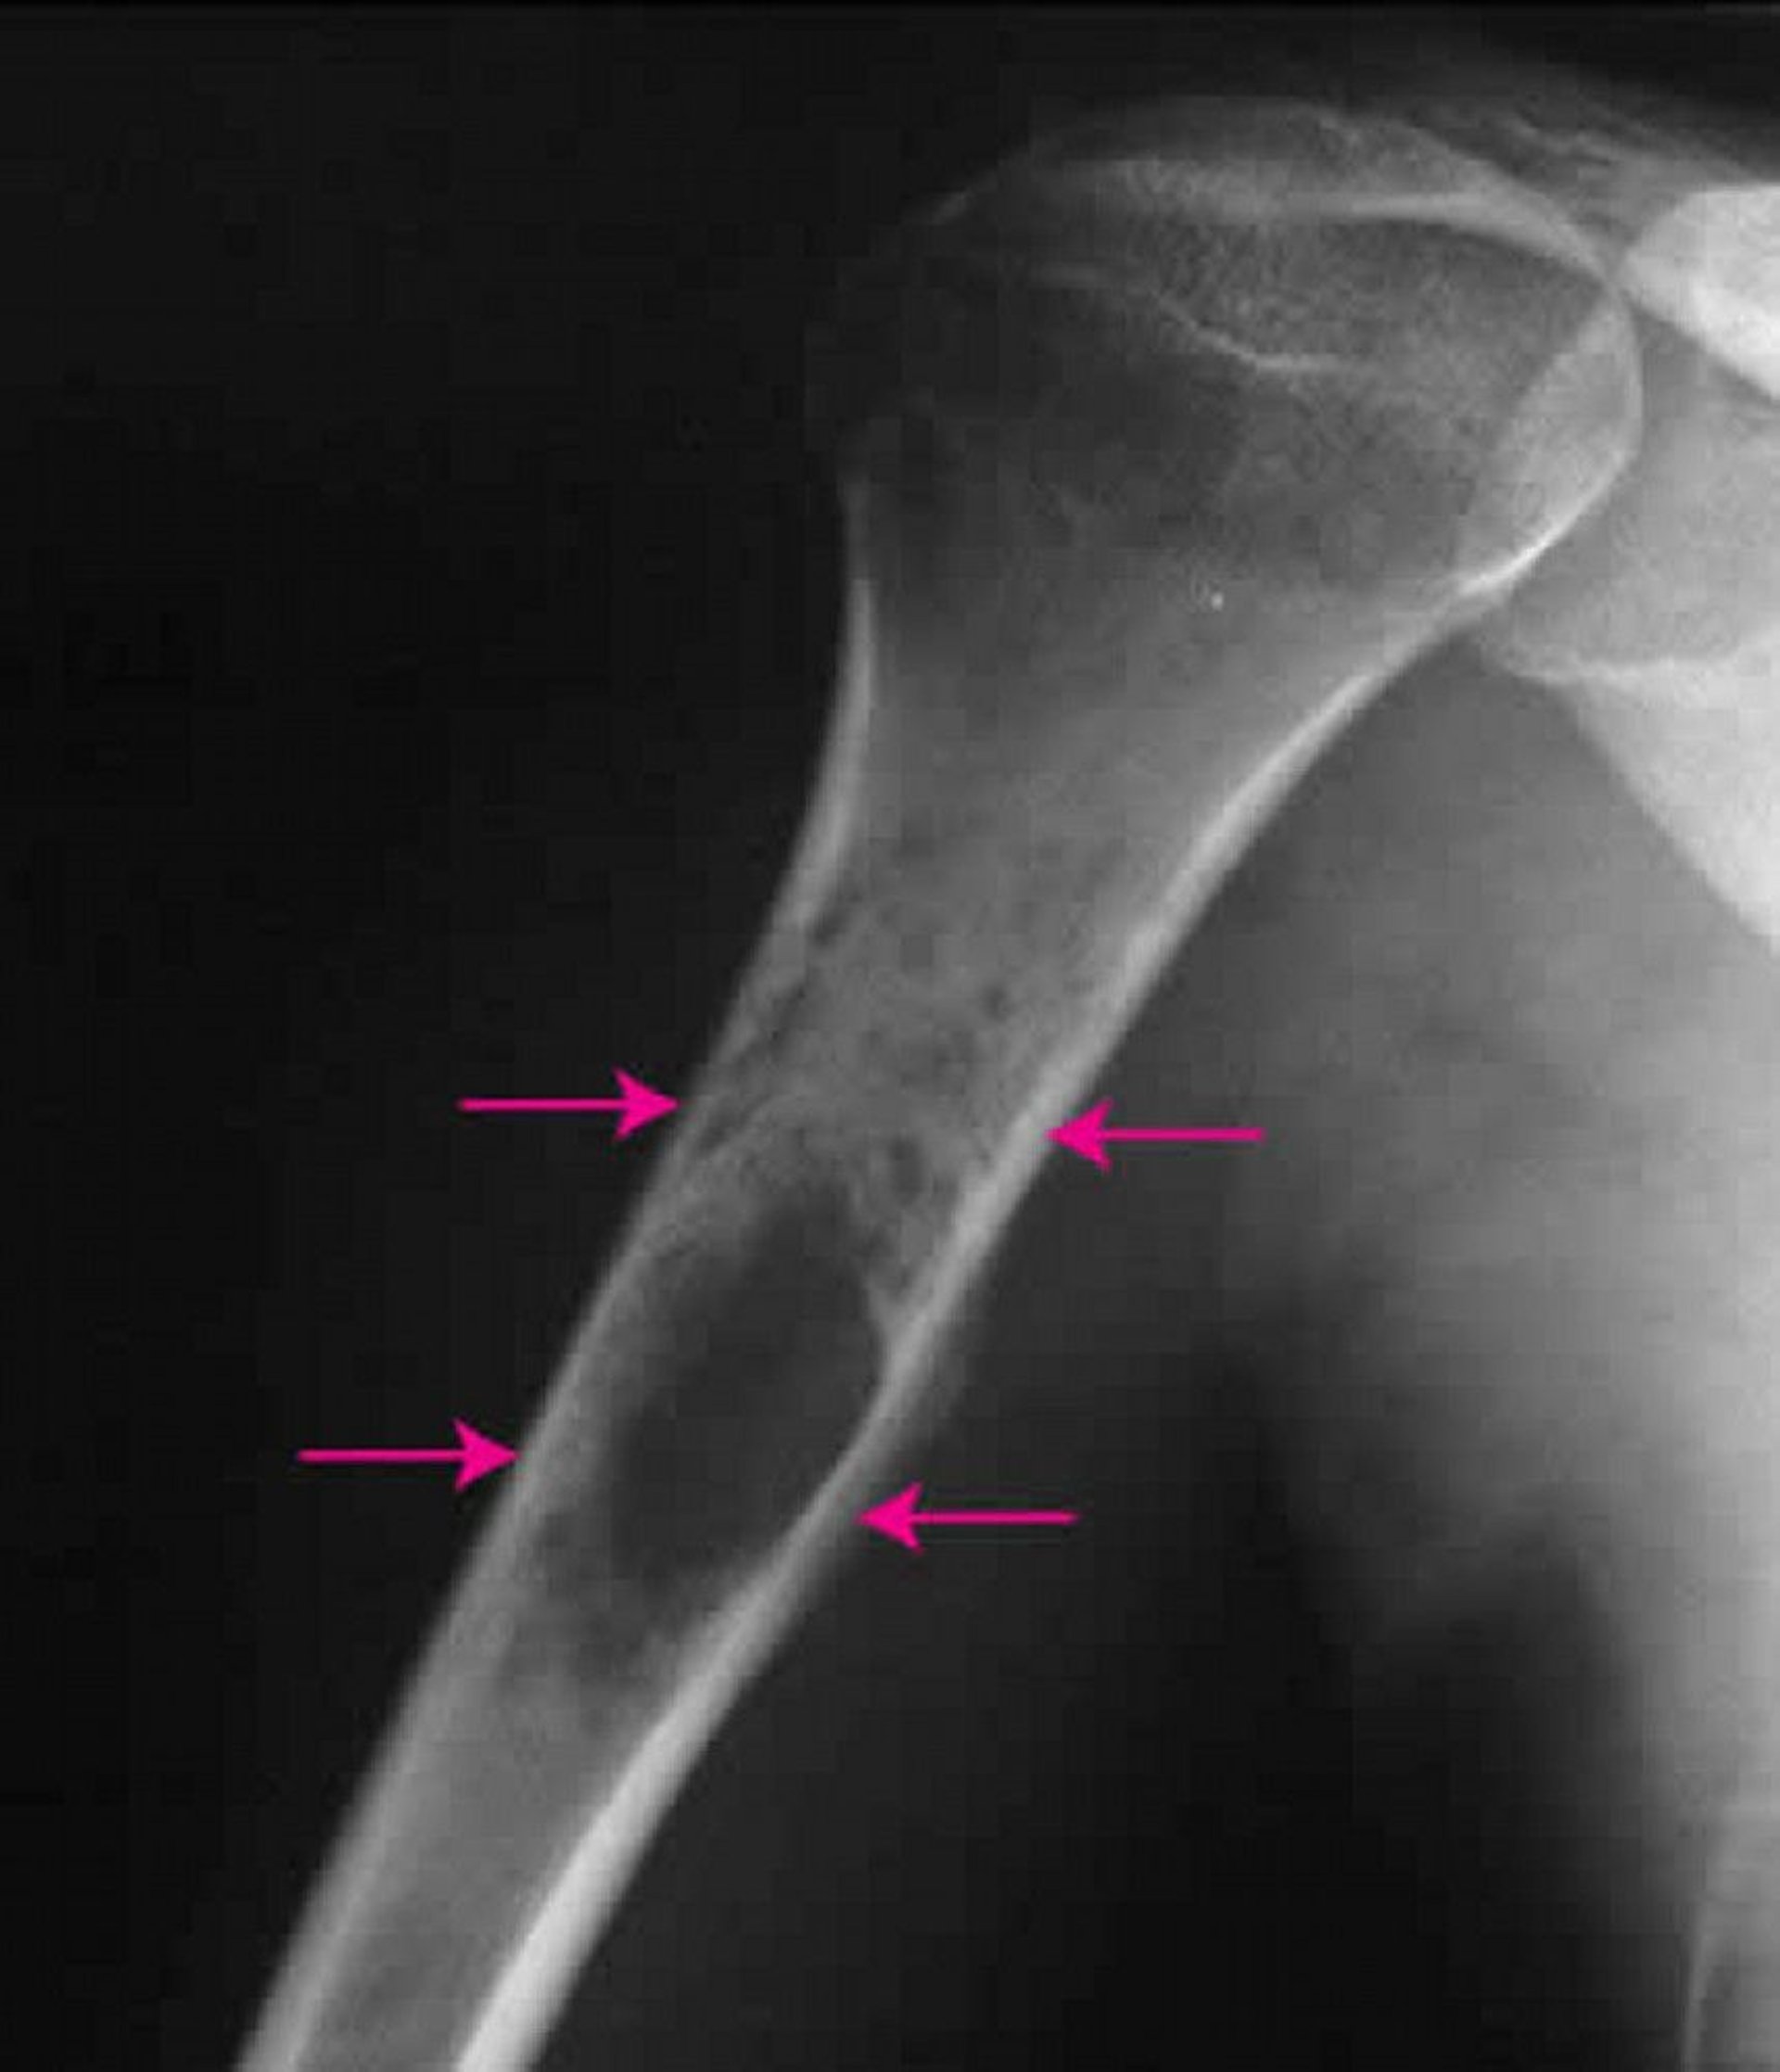

This x-ray of the shoulder shows a Ewing sarcoma (arrows) inside the upper arm bone.

Image courtesy of Michael J. Joyce, MD, and Hakan Ilaslan, MD.